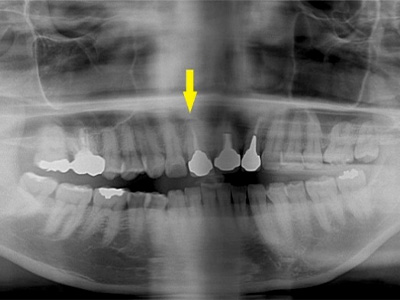

患者様は70代男性。写真は初診時の患者様のレントゲン写真です。

左右とも、上顎第一大臼歯を失っていました。

通常のレントゲン写真では骨量が十分かと思われましたが、CTを撮影してみると黄色の矢印部位、左側では少し骨の高さが足りませんでした。 -

CTを撮影して測定すると、右側はギリギリ10mmぐらいの高さで、左側は6mmほどしかありませんでした。